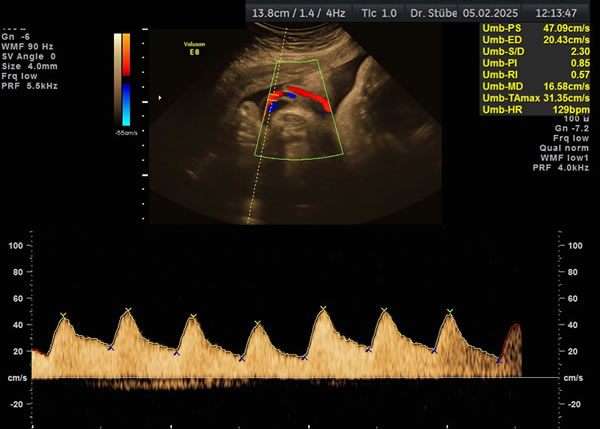

Wachstums- und Dopplersonographie

Die Dopplersonographie beinhaltet die Untersuchung der mütterlichen und kindlichen Gefäße. Sie liefert Informationen über die Versorgung des Kindes durch die Plazenta und den aktuellen Zustand des Kindes.

Dopplersonographie